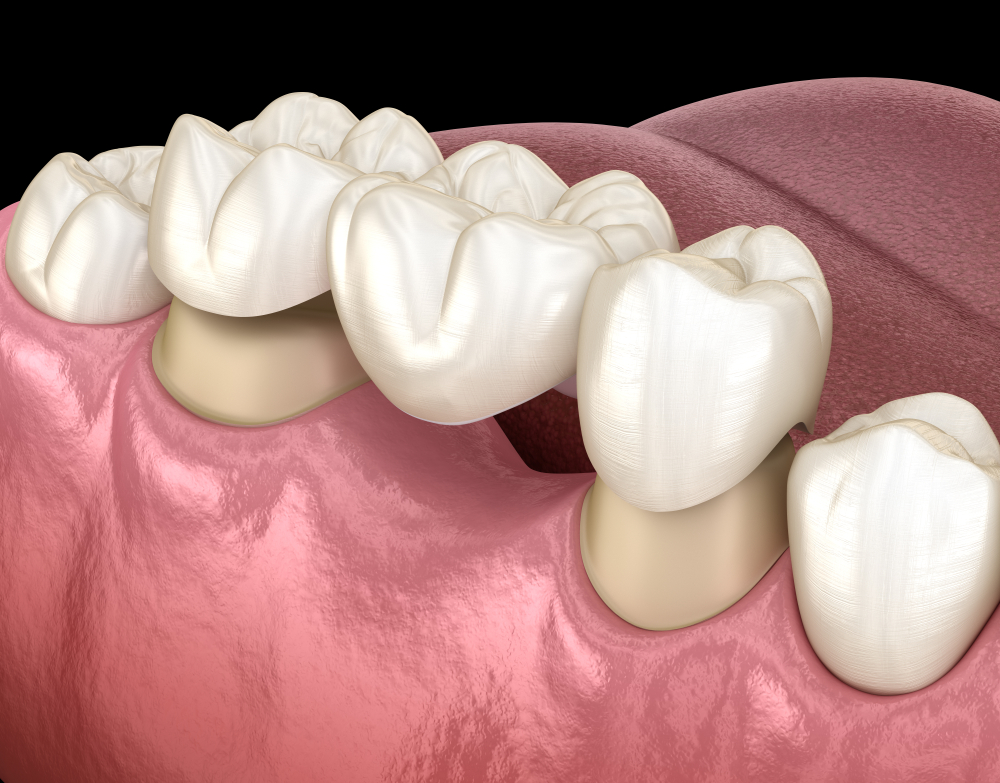

Tooth Extraction Cost in Dubai is often performed when a tooth is severely damaged or decayed beyond repair, making it unsuitable for supporting a crown or bridge. In such situations, removing the affected tooth allows for a healthy and secure foundation for future restorations. A bridge, for example, replaces one or more missing teeth, while crowns protect or strengthen individual teeth. When extraction precedes these procedures, it ensures that no weak or infected tissue interferes with the dental work.

After a tooth extraction, patients often need a replacement solution to restore the function and appearance of their smile. Crowns and bridges serve as effective restorative options. A crown covers and strengthens a weakened tooth, while a bridge replaces a missing tooth by anchoring to neighboring ones. The preparation process for these restorations includes evaluating the patient’s oral health, gum condition, and bite alignment. By carefully planning the sequence of extraction and restoration, dental professionals ensure that the final result is durable and natural-looking.

The healing process after tooth extraction is an important phase before crowns or bridges are placed. The gums and bone need time to recover fully, creating a stable foundation for the restoration. During this period, the dental professional monitors progress to ensure that the site heals evenly. Once the area has recovered, impressions or digital scans are taken to design the crown or bridge that will best fit the patient’s needs. This careful timing ensures that the restoration sits comfortably and functions effectively.

After a tooth has been removed, deciding between a crown and a bridge depends on the number of missing teeth and the health of surrounding structures. A single missing tooth may be best replaced with a crown placed over an implant or existing root. A bridge may be more suitable when multiple teeth are missing in the same area. The choice also depends on the strength of neighboring teeth and the desired aesthetic outcome. Each option aims to restore full function and maintain a harmonious bite.